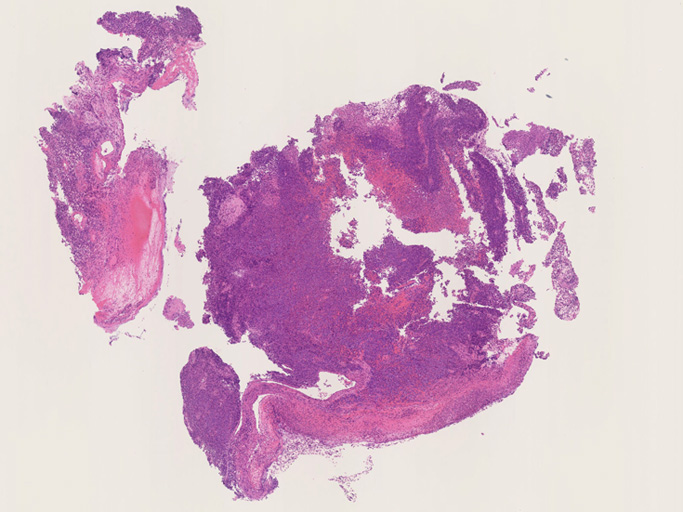

IWT case: 30歳代半ば,女性; 喫煙歴:15本/日,20歳から現在まで

当院を受診する4か月前から前胸部違和感を自覚していた. 2か月前から喘鳴を伴う咳嗽があり近医を受診.気管支喘息が疑われ加療されたが症状は改善しなかった.

経過観察中に施行された胸部CTでは左肺癌が疑われた.精査加療目的に当院呼吸器内科を紹介受診.

血液検査:腫瘍マーカー cytokeratin 19の上昇あり[14 (>3.5ng/mL)],ProGRP, CEA, CA19-9の上昇なし

CT画像:左肺から縦隔に及ぶ腫瘍(肺は単独病変. 肺内転移なし.),乳腺腫瘤,子宮腫瘤, 多発肝腫瘤あり.

処置: 気管支内視鏡検査で,1.左肺腫瘍からTBB (VS1),2.腫瘍と一塊になったリンパ節からEBUS-TBNA (VS2),を施行された.

CT画像および肺腫瘤生検組織